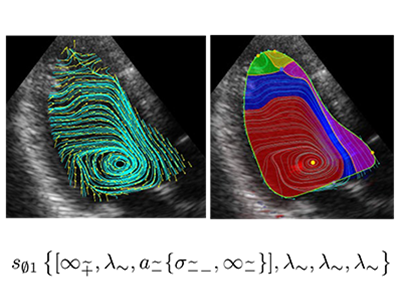

画像はリリースより

近年、心エコーや心臓MRIなどの医療用画像診断機器で血流が可視化できるようになり、心臓の渦血流は心不全などでは回転が弱くなることなどが観察されてきた。しかし、単に複雑な渦血流をただ観察しているだけでは、その渦血流が効率良く血液の拍出に貢献しているかを定量的に評価できないため、流れのパターンを正確に抽出する必要があった。

坂上教授と板谷准教授は2017年より共同研究を開始し、心臓の血流画像で示される渦血流に流線トポロジー解析を適用することを検討した。特に、心臓の中で発生する渦血流は効率よく血液を全身に駆出するために必要であるとされる一方で、1回の心拍の間に複雑な様相の渦血流が観察され、それらが次々と発生しては消滅することを繰り返すため、客観的に渦血流のパターンを定義し抽出することが難しく、心疾患を評価することからはかなり遠いという現実があった。こうして両者は、心臓ではダイナミックに運動する心筋や心臓弁の運動により血流が発生しているため、これまでの流線トポロジーの理論をそのままは適用できないという問題に直面した。

研究グループは、流れの圧縮性の問題点(1)を、従来の非圧縮流体での TFDAの理論を数学的に拡張することにより解決。動く境界条件の問題点(2)は、左心室の境界を1点に貼り合わせるという数学的操作により、「退化特異点」と数学的には呼ばれる流れ場として理論に取り込むことで解決した。また、心エコー画像などの診療用装置から得られた画像データに対して、上述の理論と矛盾しないように、データを補正する位相的前処理(Topological pre-conditioning)という数学的な処理を施すことを試みた。

渦血流の渦構造・心臓機能・病態を、新たに定義した位相的渦構造で評価可能に

これにより、心血流エコーやMRIから得られる流線画像データに対して適用できる流線トポロジカルデータ解析の数学理論が完成した。これを用いると、心エコーVFM(Vector Flow Mapping)によって得られる健常例の左室心尖部の長軸断面で得られる収縮期血流画像から特徴的な位相構造を抽出して数学的に分類し、そのパターンに固有の文字列表現を割り当てることができた。このCOT表現後に一部の特定文字列が心臓血流内部の特定渦領域を表現するため、これを「位相的渦構造」として、数学的にも曖昧さなく定めることができるという。このような心血流エコー画像をトポロジカルデータ解析する技術開発は世界初となる。この結果、これまで明確な定義がなかった心臓血流が作り出す渦血流に、TFDAは「位相的渦構造」と呼ばれる新しい概念を定義することに成功。さらに、このことにより、渦構造と心臓のポンプとしての機能や心疾患の病態を、位相的渦構造で評価可能となった